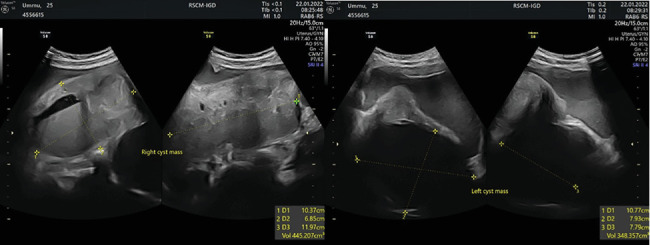

子宫内膜异位囊肿是常见的,但双侧巨大子宫内膜异位囊肿无症状的病例极为罕见。破裂也不常见,但当它发生时,它可以模仿阑尾炎或异位妊娠,由于腹膜刺激,往往需要紧急干预。一位25岁的女性表现为恶心,呕吐,腹部肿块增大。超声示双侧卵巢囊性肿块,有磨砂玻璃样及游离肝下液。尽管初步复苏,但由于症状恶化,进行了紧急剖腹探查术。术中发现右侧卵巢囊肿(20 × 15 × 15 cm)破裂,伴子宫后缘、直肠及右侧卵巢窝广泛粘连,同时左侧卵巢子宫内膜异位囊肿(12 × 10 × 10 cm)。患者行右侧输卵管卵巢切除术、左侧膀胱切除术及输尿管溶解术。组织病理学证实子宫内膜异位囊肿。快速手术干预是至关重要的破裂囊肿,以减少粘连的形成和保持生育能力。术后,持续的激素治疗,如口服黄体酮或宫内节育器,建议减少复发。

Endometriotic cysts are common, but bilateral giant endometriosis cyst with asymptomatic cases are extremely rare. Rupture is also uncommon, yet when it occurs, it can mimic appendicitis or ectopic pregnancy due to peritoneal irritation, often requiring emergency intervention. A 25-year-old woman presented with nausea, vomiting, and an enlarging abdominal lump. Ultrasonography revealed bilateral ovarian cystic masses with ground glass appearances and free subhepatic fluid. Due to worsening symptoms despite initial resuscitation, emergency exploratory laparotomy was performed. Intraoperatively, a ruptured right ovarian cyst (20 × 15 × 15 cm) with extensive adhesions to the posterior uterus, rectum, and right ovarian fossa was identified, along with a left ovarian endometriotic cyst (12 × 10 × 10 cm). The patient underwent right salpingo-oophorectomy, left cystectomy, and ureterolysis. Histopathology confirmed endometriotic cysts. Rapid surgical intervention is crucial in ruptured cysts to minimize adhesion formation and preserve fertility. Postoperatively, continuous hormonal therapy, such as oral progesterone or an intrauterine device, is recommended to decrease recurrence.